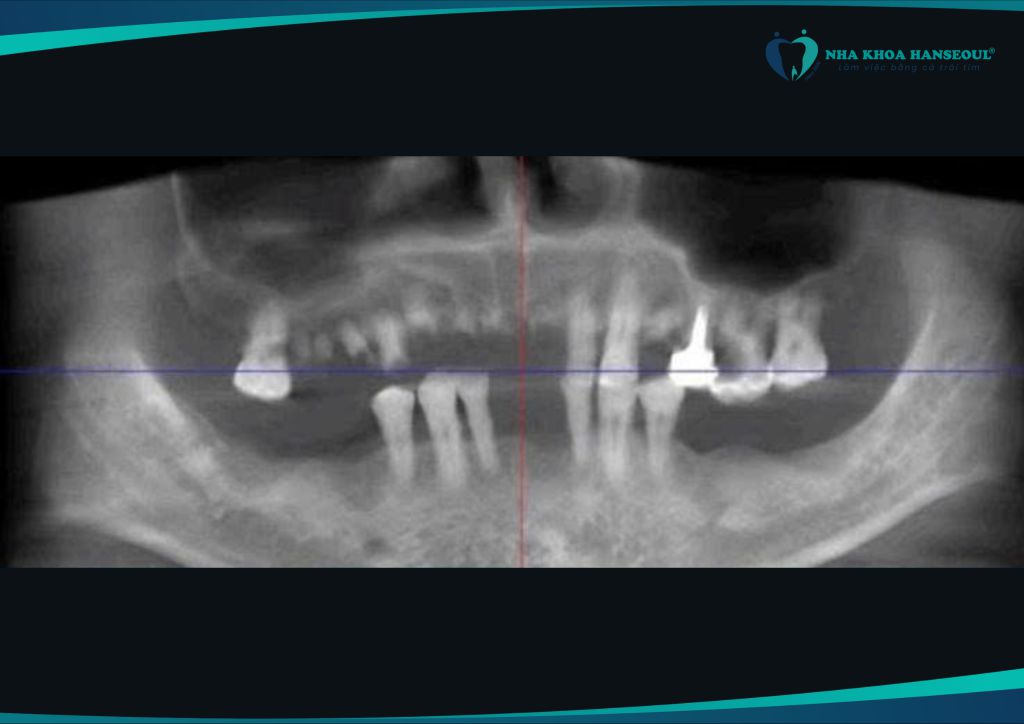

- Chụp phim CT ConeBeam 3D

- Xét nghiệm máu, nội tiết, tim mạch, hô hấp

- Đo mật độ xương hàm, đánh giá khả năng tích hợp trụ

Nhờ vào kết quả chi tiết này, bác sĩ có thể lập kế hoạch điều trị cá nhân hóa, đồng thời dự phòng biến chứng trong và sau phẫu thuật.